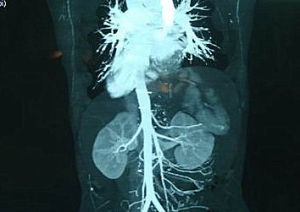

鏡面人內臟圖像胚胎在發育的過程中,不同內臟發育的時間是不一樣的。但孕期八周之內,各個內臟原基就奠定了,這是質的變化,八周之後,開始量的變化,內臟發育長大。毫無疑問,“鏡面人”的內臟是在孕期八周之內就決定了。